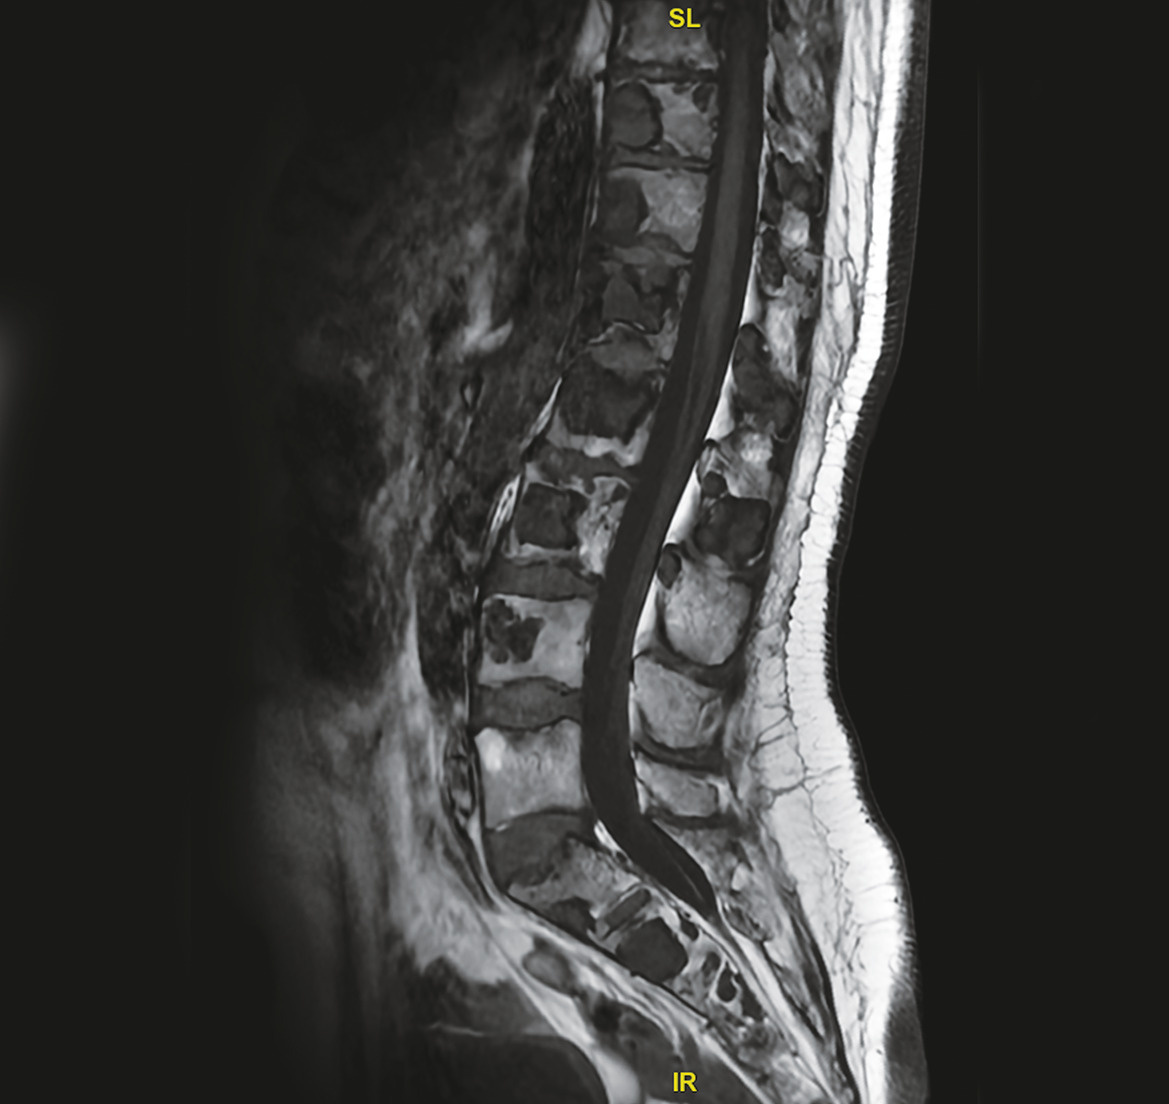

Les images IRM (fig. 1 et 2) du rachis montrent de multiples lésions vertébrales en hyposignal T1 et en hypersignal T2 hétérogène, atteignant à la fois les corps vertébraux et les arcs postérieurs. L’atteinte du rachis est ubiquitaire, prédominant en lombaire avec des zones lytiques et de signal liquidien.